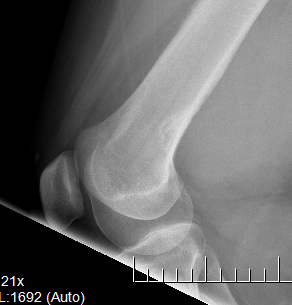

Osteofibrous DysplasiaAdamantinomaEwings

OFD                    Adamantinoma                                Ewings

• Diaphyseal lesions